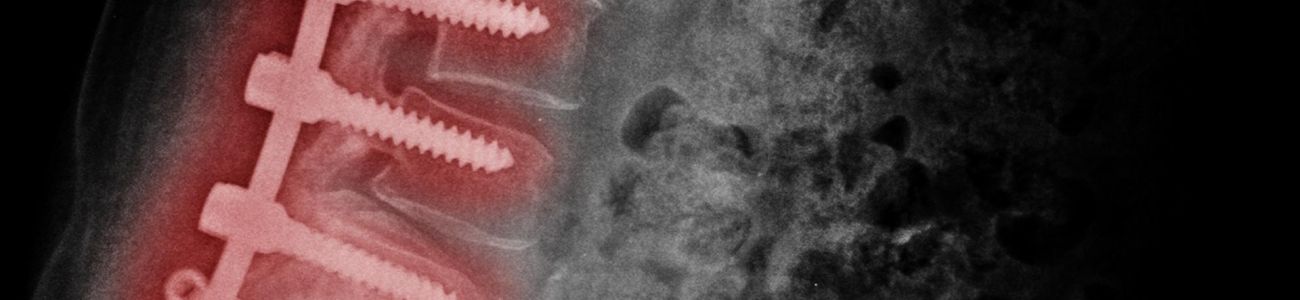

Além dos enxertos, outros materiais podem ser utilizados pelos especialistas, como parafusos e implantes metálicos. A principal vantagem do uso desses materiais que são feitos, principalmente de titânio para resistência e compatibilidade com o organismo, é poder dispensar a imobilização externa após a artrodese lombar.